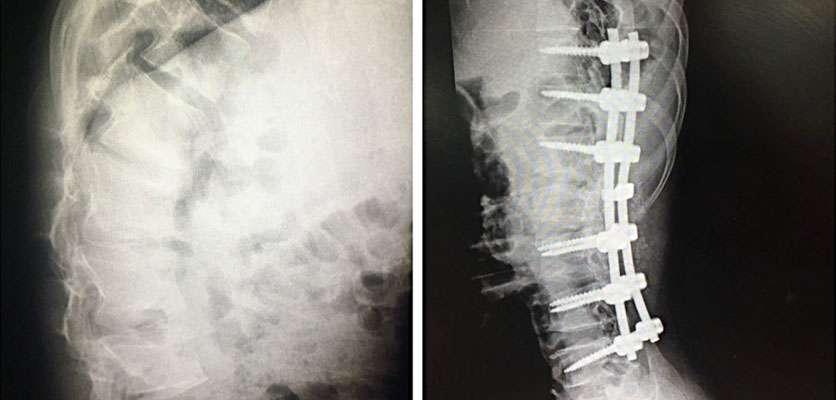

درمان جراحی

متناسب با اینکه فشاربرنخاع ازقسمت جلوی ستون مهره ها و یا خلف ستون مهره بیشتر است.drgholenj شکل 1بهترین فیزیوتراپی در اصفهان

سه روش جراحی برای تنگی کانال نخاعی گردن انجام می شود:

1.لامینکتومی ( برداشتن لامینا یا قسمت پشت ستون مهره ها)

1. دیسککتومی(برداشتن دیسک)

2. کورپکتومی